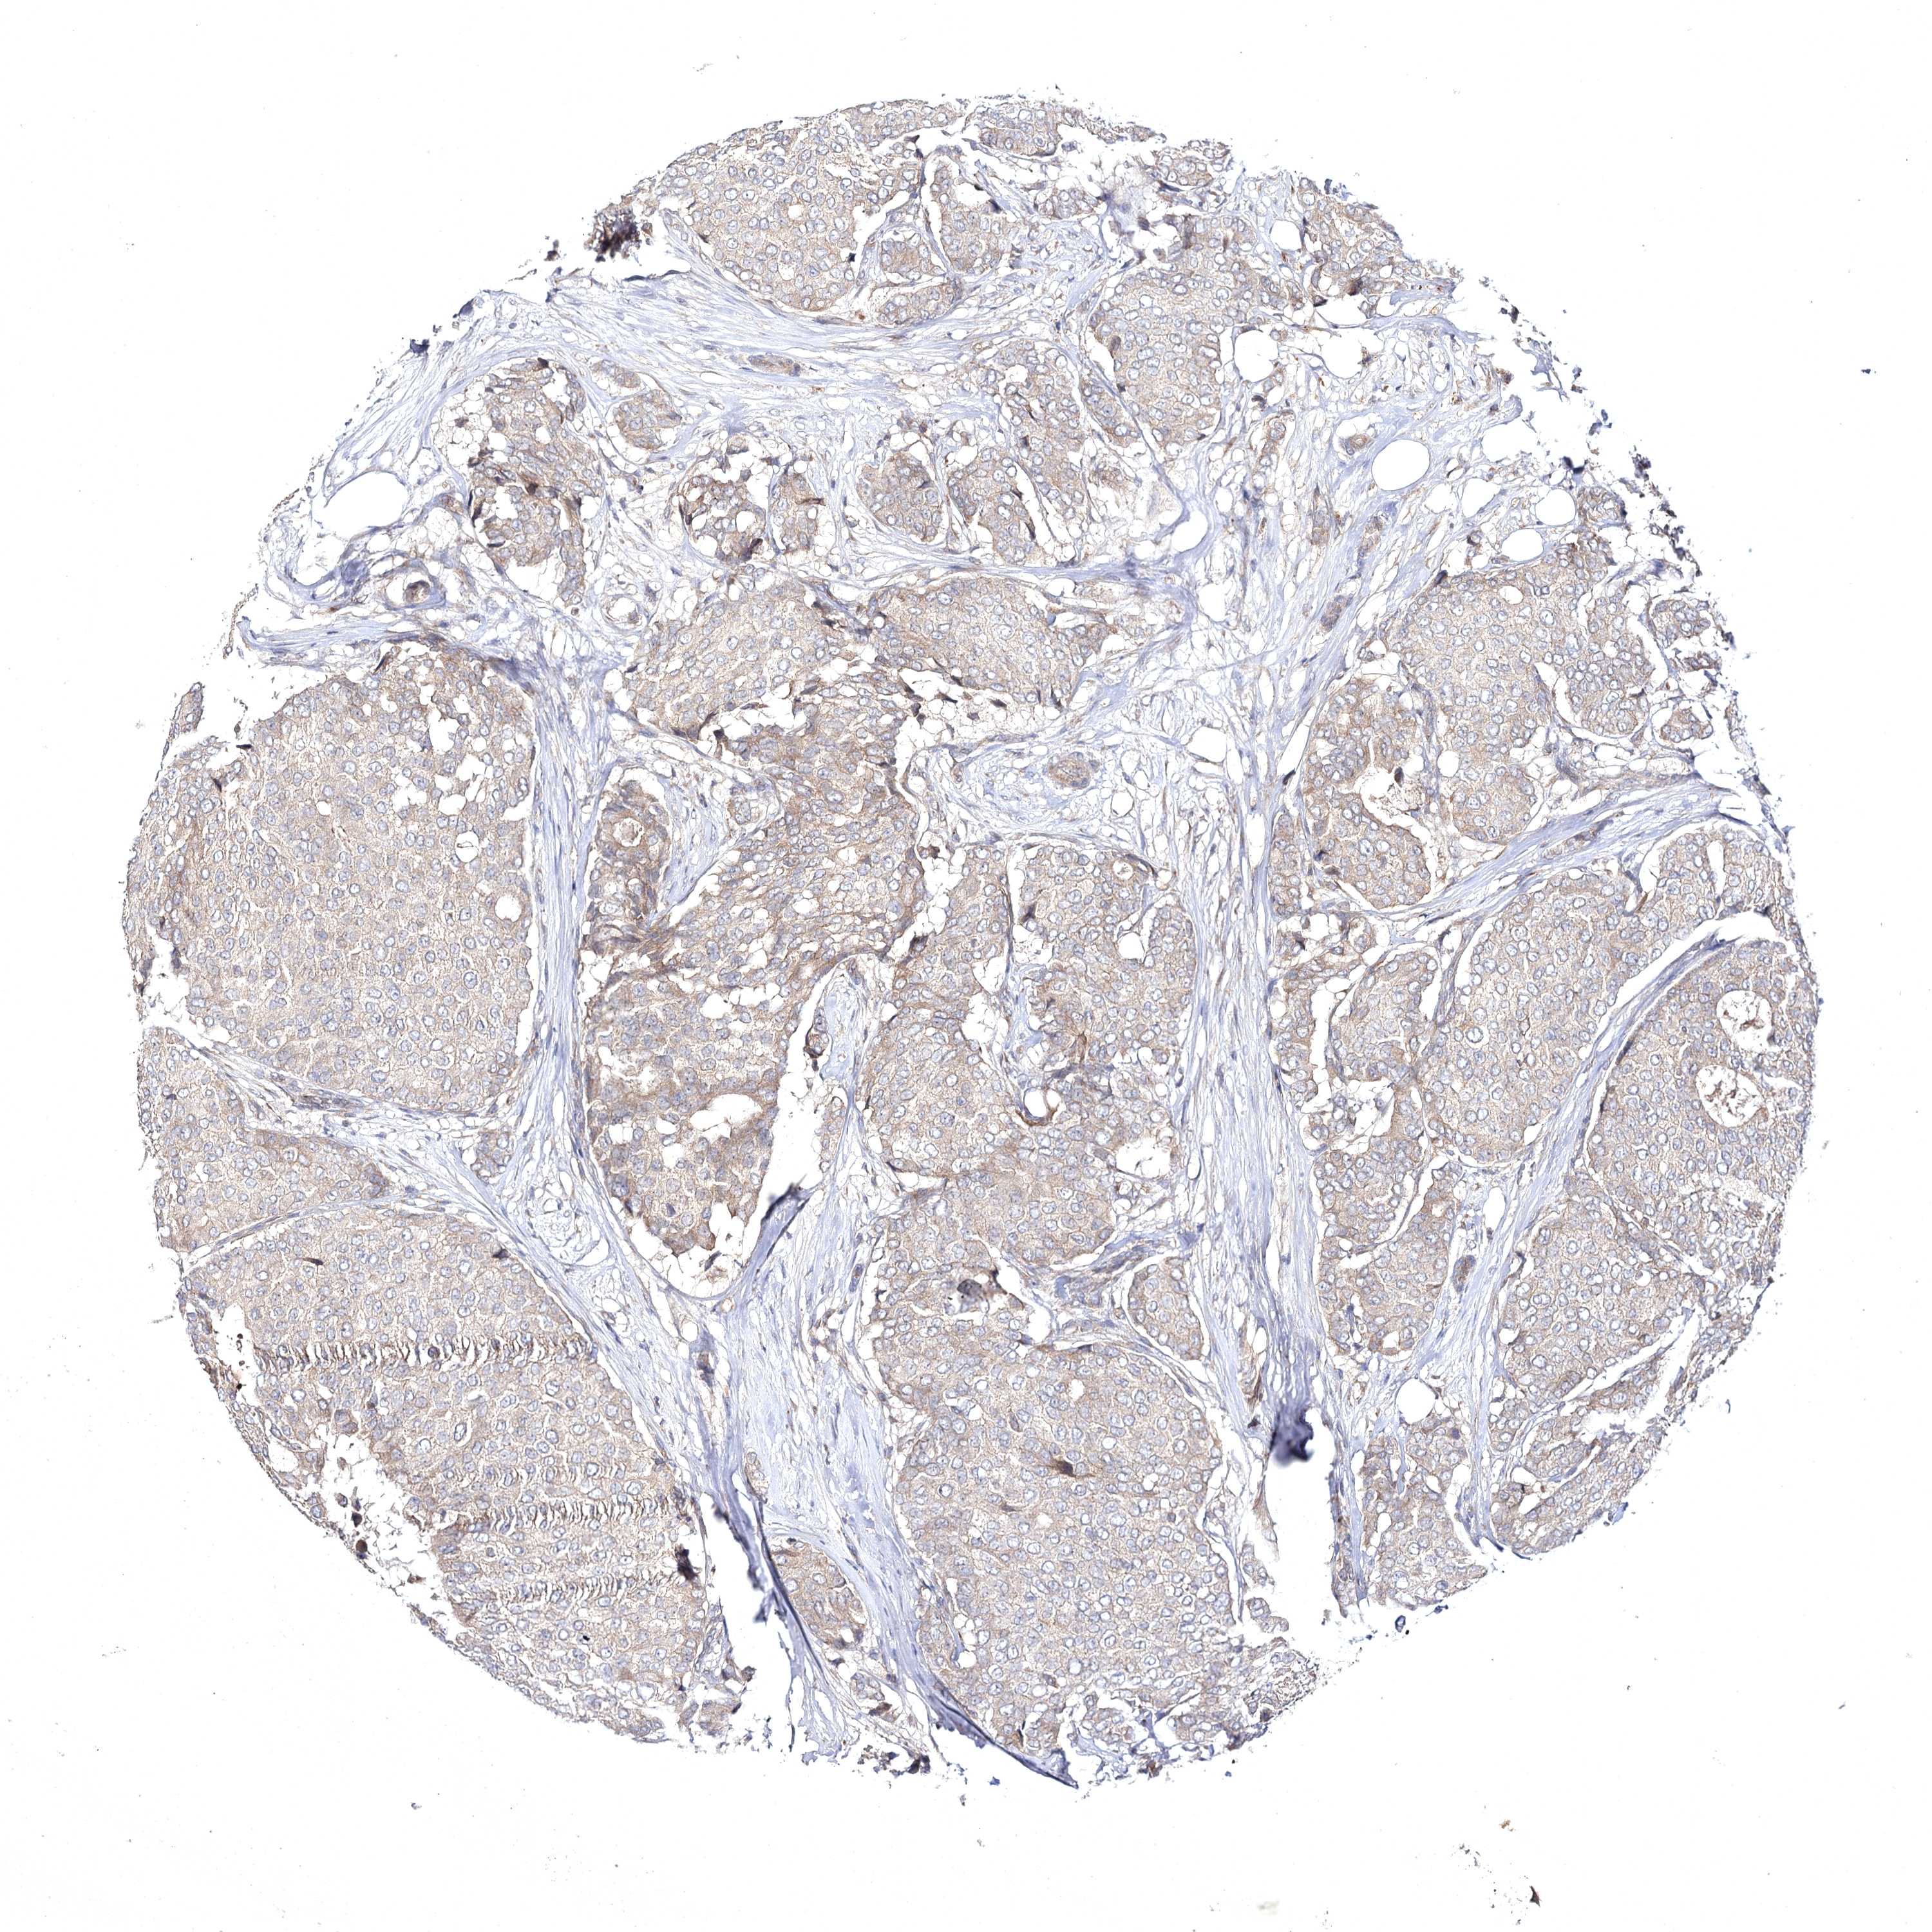

CANCER BREAST CANCER Show tissue menu

Breast cancer

Human cancer